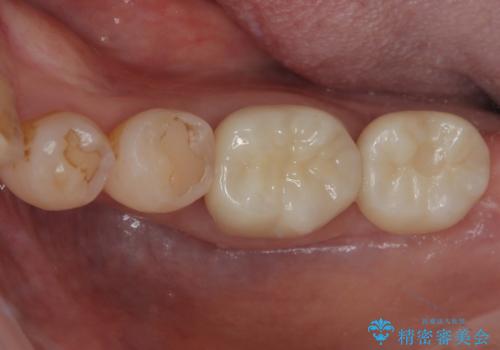

銀歯の下の虫歯|オールセラミッククラウン|歯を長持ちさせるための治療|歯の神経を守る

担当医 河野豊嘉